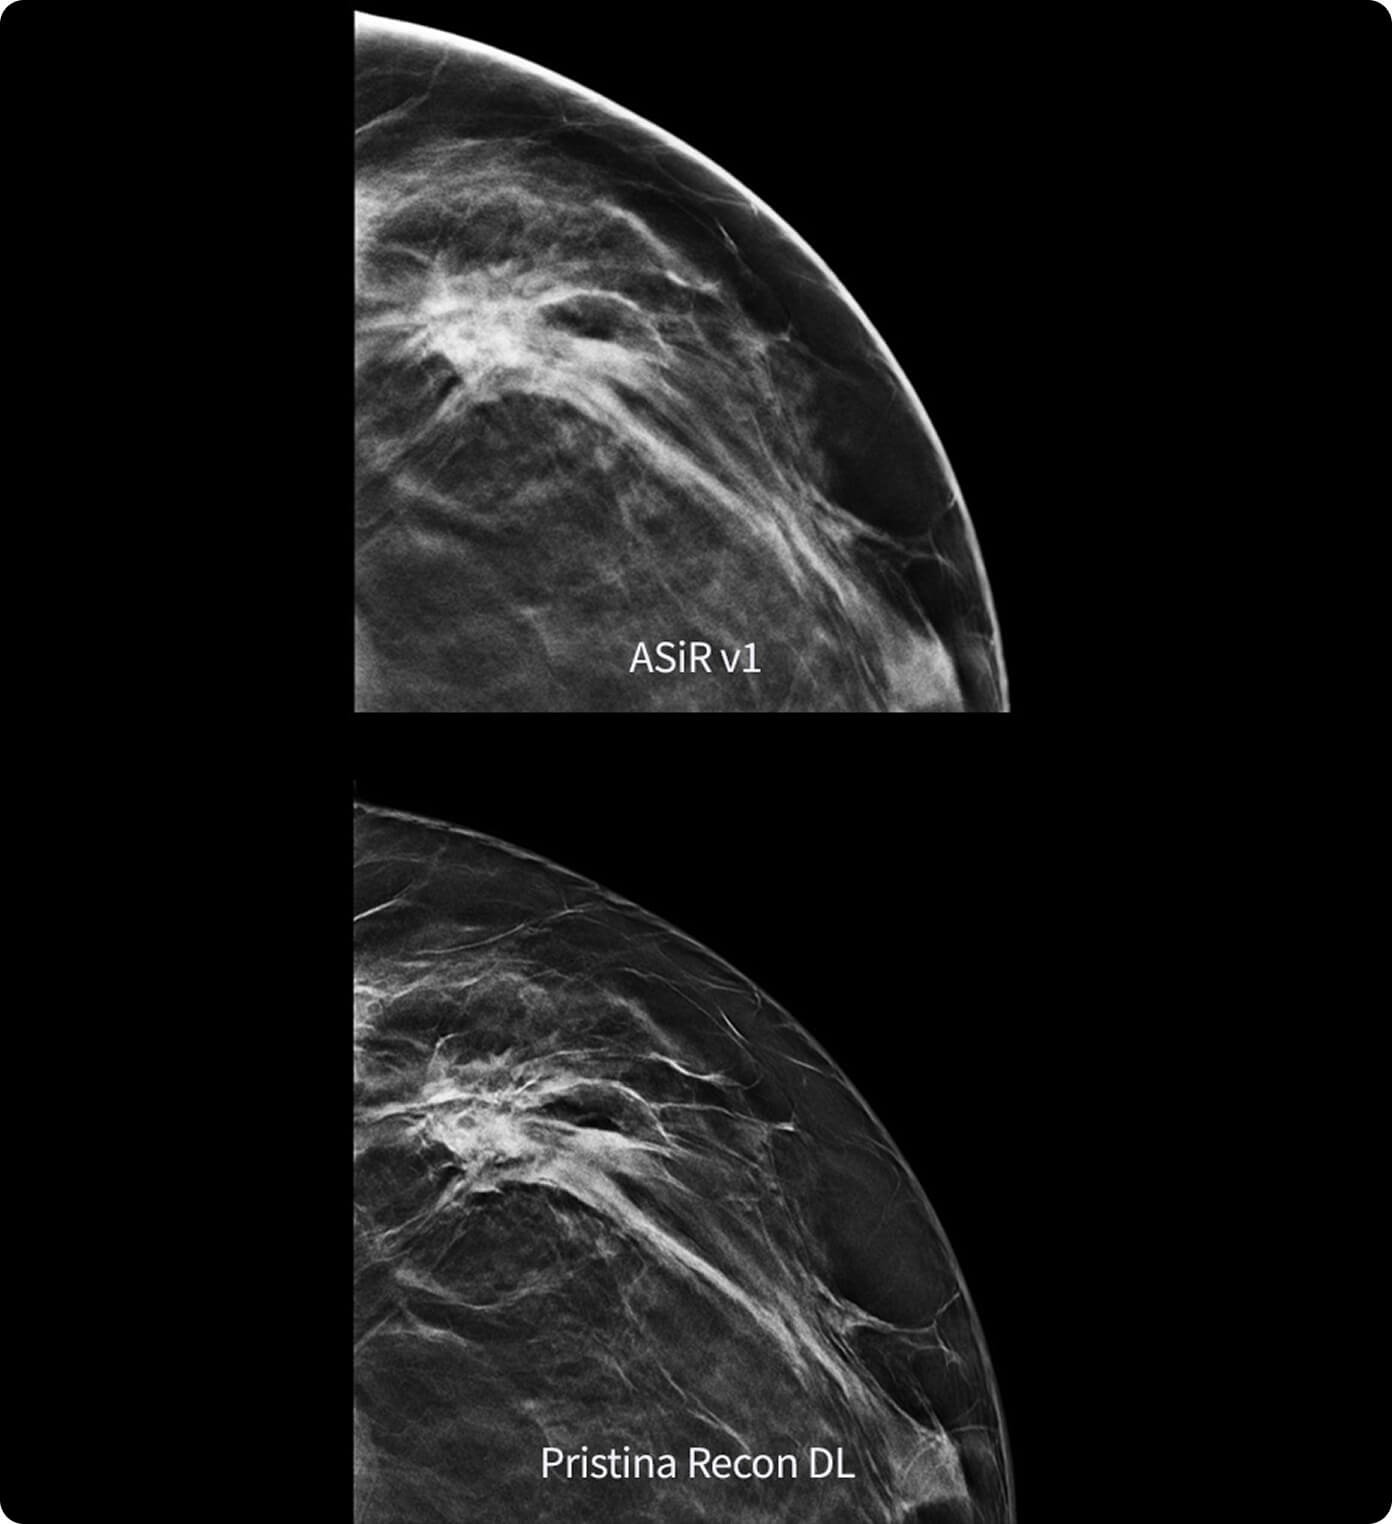

Shadow Reduction

Confident answers